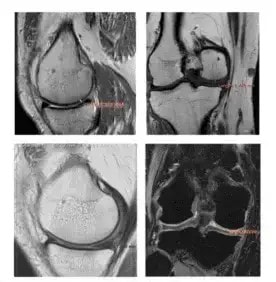

Specialiștii dar și pacienții cu “experiență” în artroză, pot identifica câștigul de grosime a țesutului articular comparând imaginea de sus cu cea de jos respectiv aceeași incidentă a articulației investigate RMN înainte de administrarea terapiei Rigenera în artroză și apoi la 3 ani după tratament.

Fiecare calup de imagini reprezintă câte un pacient investigat cu incidență frontală și laterală. Detalii suplimentare în marginea inferioară a fiecărei imagini - interpretarea imaginilor se face pe 1/2 stânga sus versus jos și 1/2 dreapta sus versus jos. Cuvinte cheie: RMN tratament artroza

Câștig (stânga) de la 1,064 mm la 1,226 mm respectiv (dreapta) de la 1,223 mm la 1,555 mm

Câștig (stânga) de la 1,339 mm la 1,472 mm respectiv (dreapta) de la 1,489 mm la 1,822 mm

Câștig (stânga) de la 1,068 mm la 1,263 mm respectiv (dreapta) de la 0,893 mm la 1,914 mm